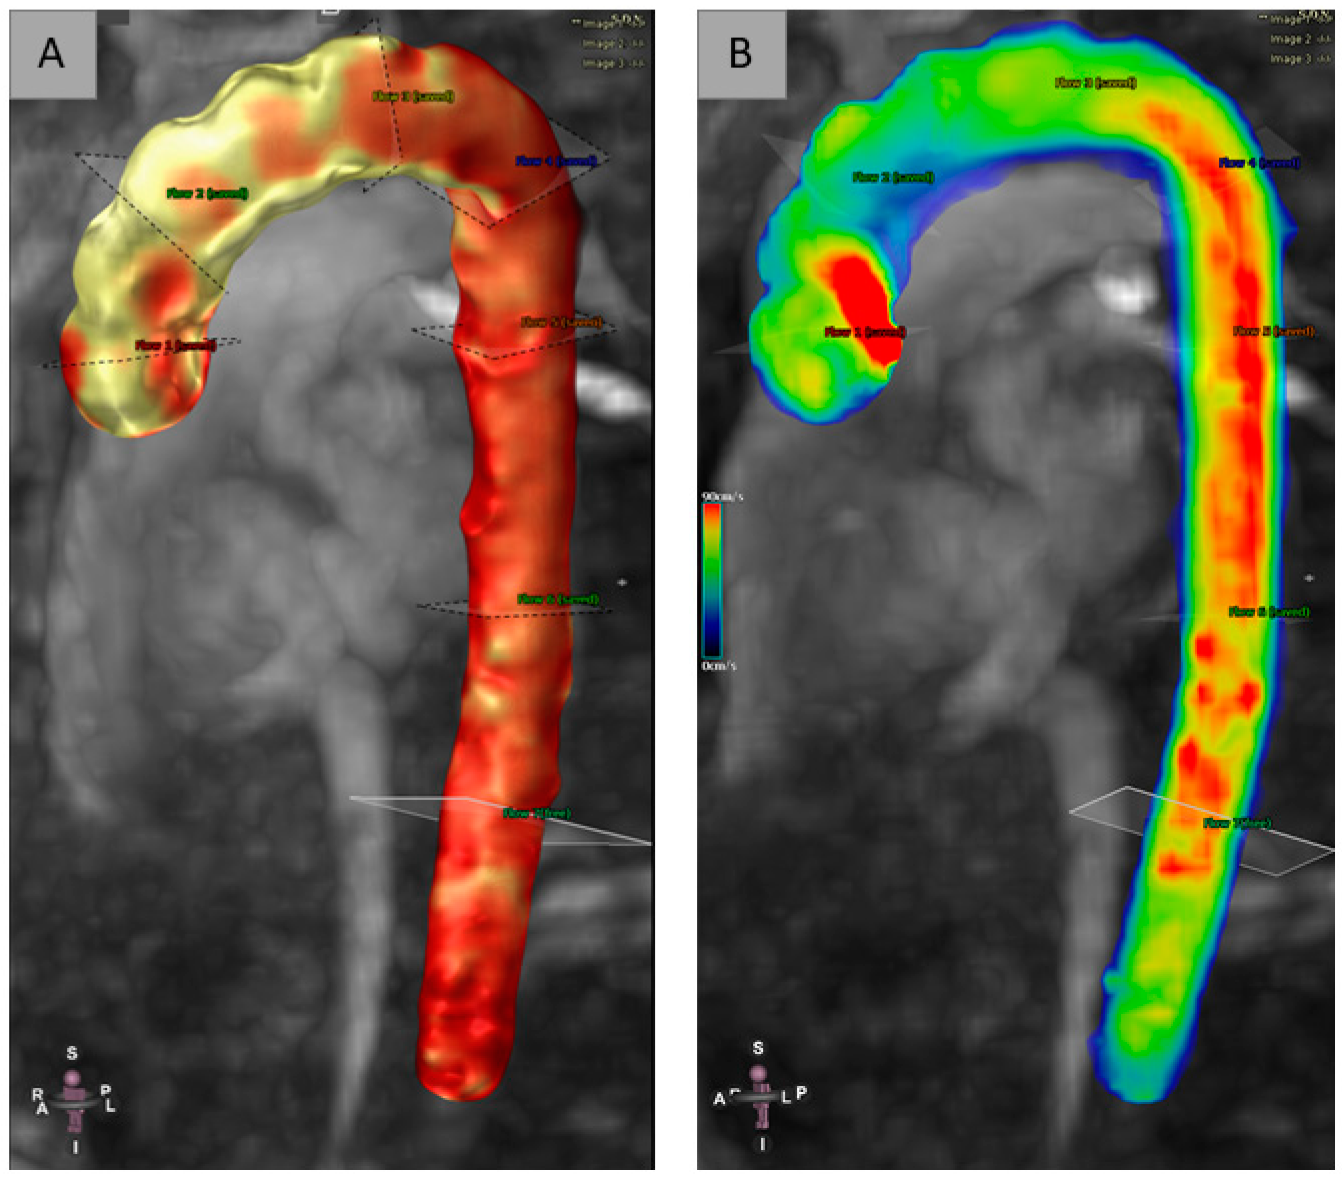

The EACVI Textbook of Cardiovascular Magnetic Resonance (The。4D-Flow Cardiovascular Magnetic Resonance Sequence for。Cardiovascular magnetic resonance physics for clinicians。在庫整理に伴う、出品です。表紙:きれい中身:きれい商品の状態は、中身の状態です梱包:緩衝剤リサイクル利用大型本の為、宅急便での発送となります。4D Flow cardiovascular magnetic resonance consensus。古いものですので時間経過によるシミ等についてはご理解下さい。J.M. Coetzee & Paul Auster 洋書セット。ストレンジャーシングス イレブン役 ミリー ボビー ブラウン 直筆サイン本。#洋書ぐぐ